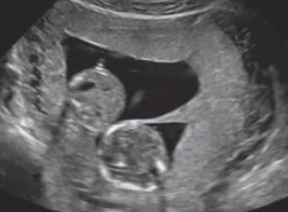

Considerando uma paciente do sexo feminino, 33 anos, com Beta HCG positivo, analise a seguinte imagem do ultrassom e assinale a alternativa correta.

Enunciado 4535191-1